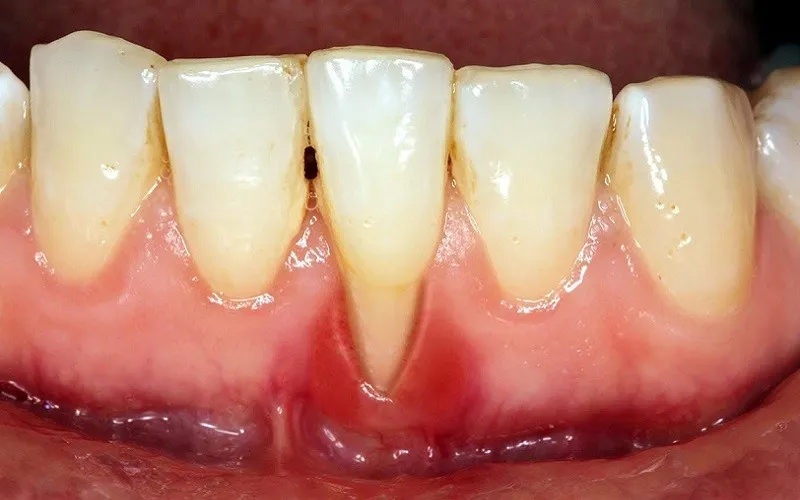

Răng Mòn và Viêm Lợi

Khi răng có dấu hiệu dài ra, nguyên nhân thường liên quan đến tình trạng tụt nướu hoặc mòn men răng. Điều này khiến phần chân răng lộ ra, làm răng trở nên nhạy cảm hơn khi ăn uống nóng lạnh. Đồng thời, tụt nướu cũng tạo điều kiện cho vi khuẩn tích tụ, dễ dẫn đến viêm lợi, chảy máu chân răng và nếu kéo dài có thể tiến triển thành bệnh nha chu ảnh hưởng đến độ chắc khỏe của răng.

Răng Dài Quá Mức

Khi nhận thấy răng lộ ra nhiều bất thường, nướu tụt rõ hoặc tỷ lệ răng – nướu mất cân đối, đó là dấu hiệu cần được kiểm tra chuyên môn. Tình trạng răng dài quá mức không chỉ ảnh hưởng đến thẩm mỹ mà còn làm tăng nguy cơ nhạy cảm răng và bệnh lý nha chu. Việc tham khảo ý kiến nha sĩ sẽ giúp xác định nguyên nhân chính xác và lựa chọn phương pháp điều trị phù hợp, tránh để tình trạng tiến triển nặng hơn.